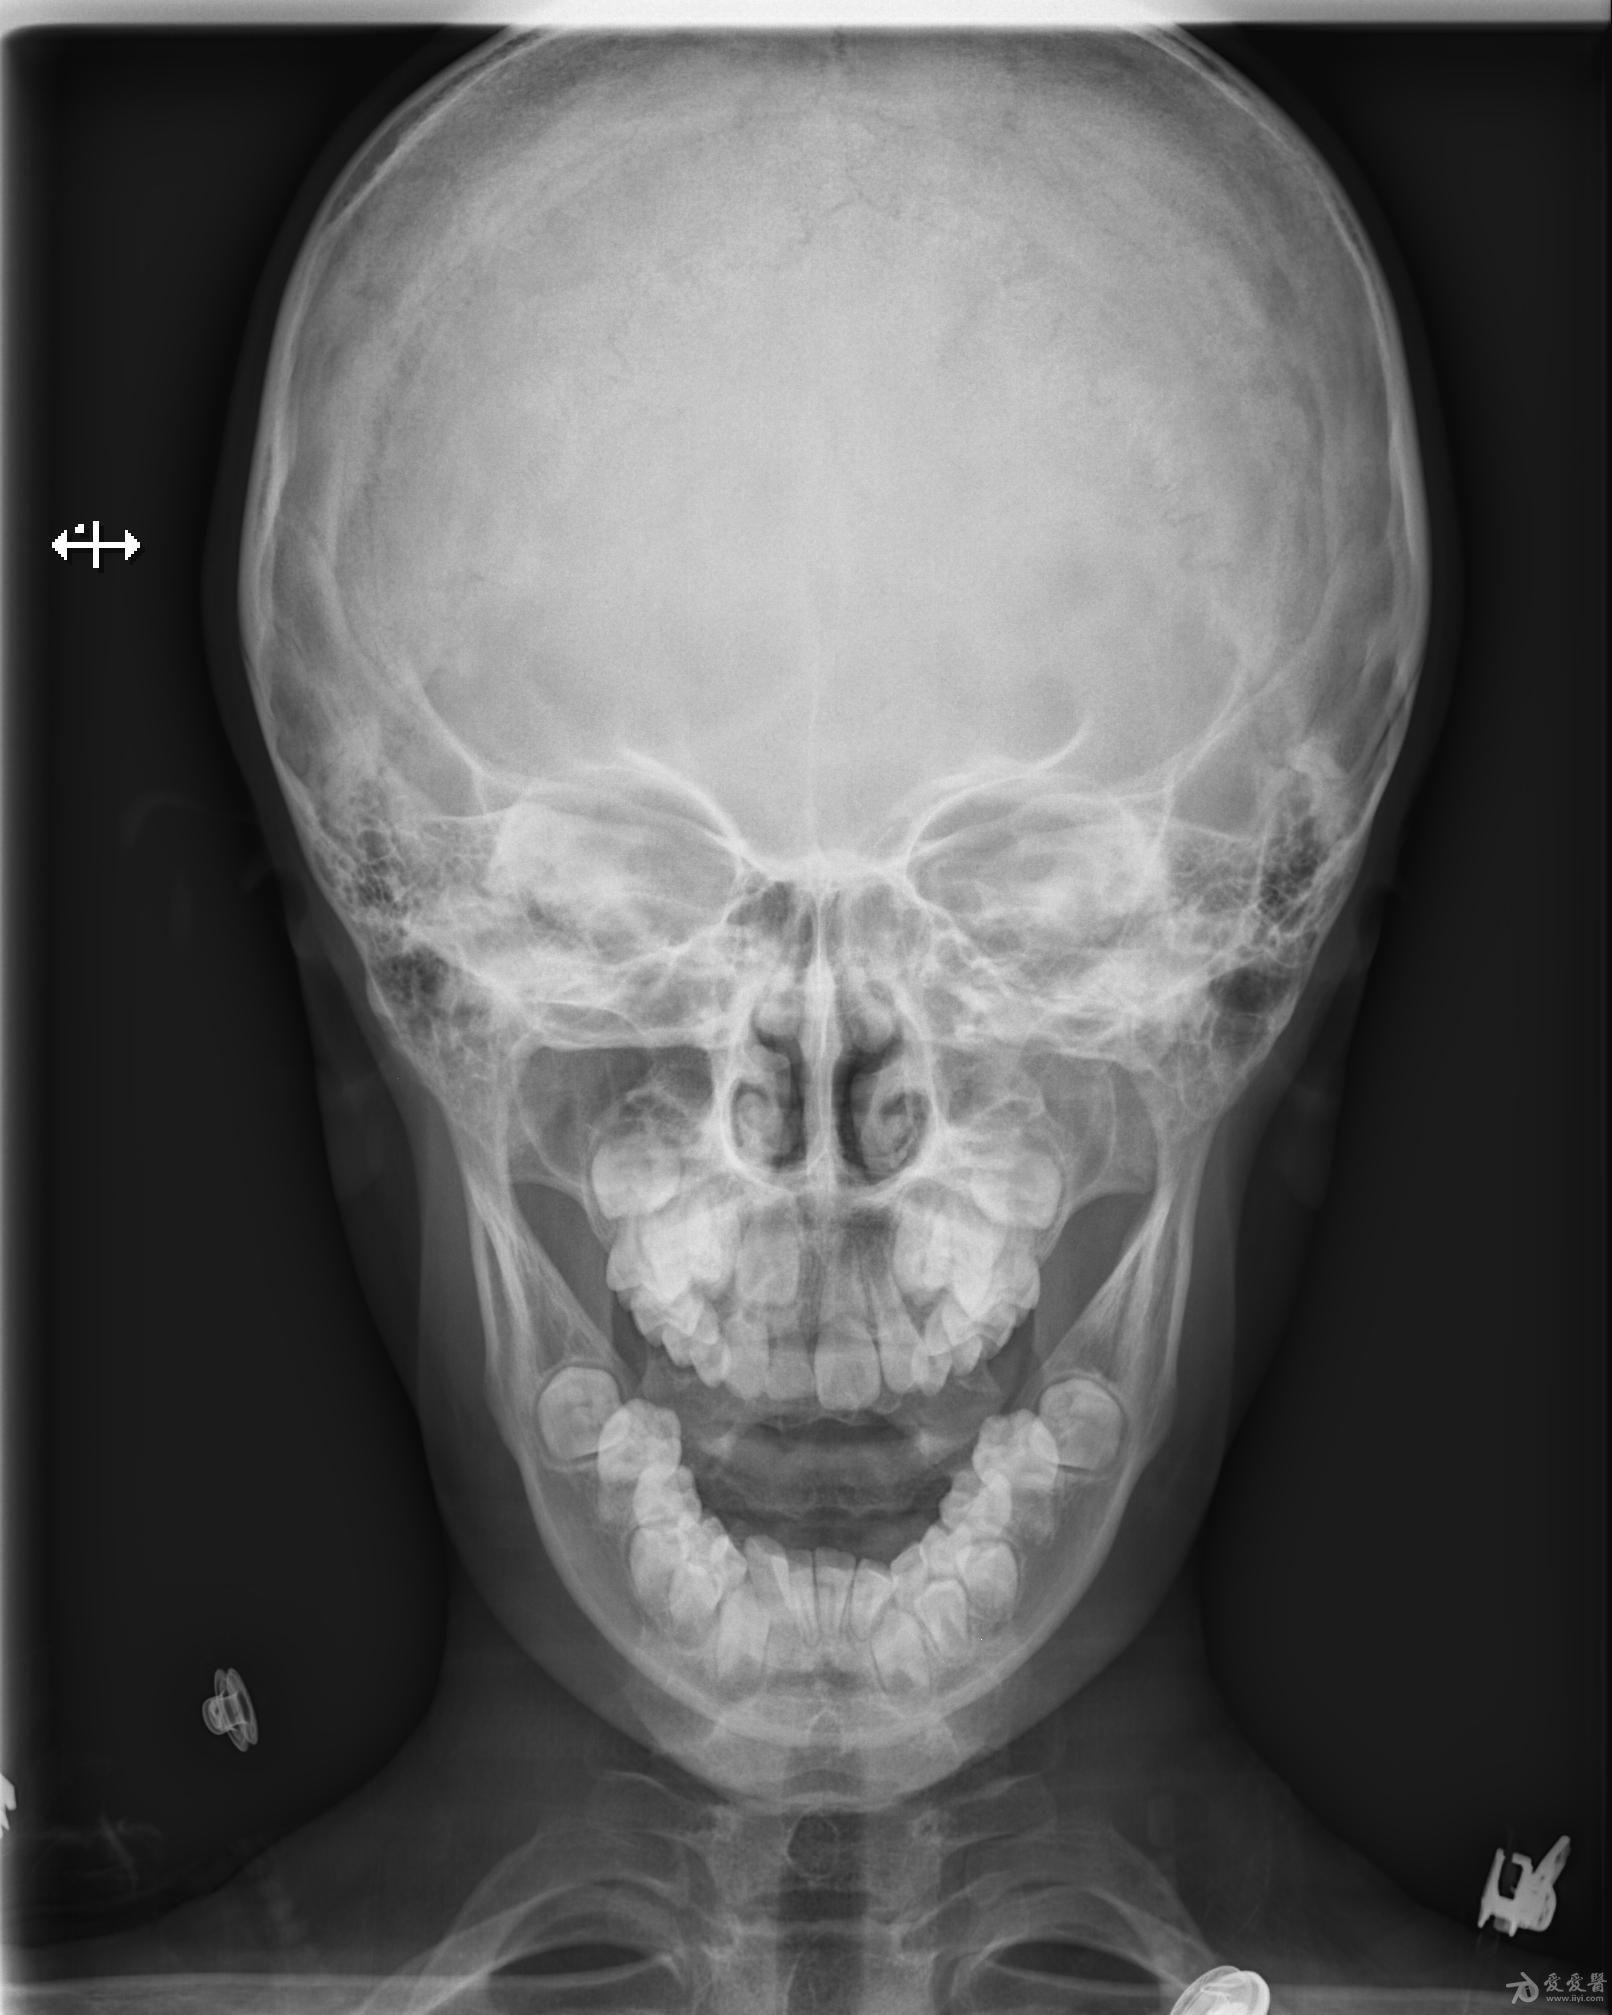

男,9岁10个月,右侧中切牙乳牙未换,右侧切牙已换。牙片显示右中切牙恒牙位置异常,与右侧切牙(恒牙)部分重叠,且右中切牙恒牙牙根稍短小(位置影响?),如何处理?能否矫正?